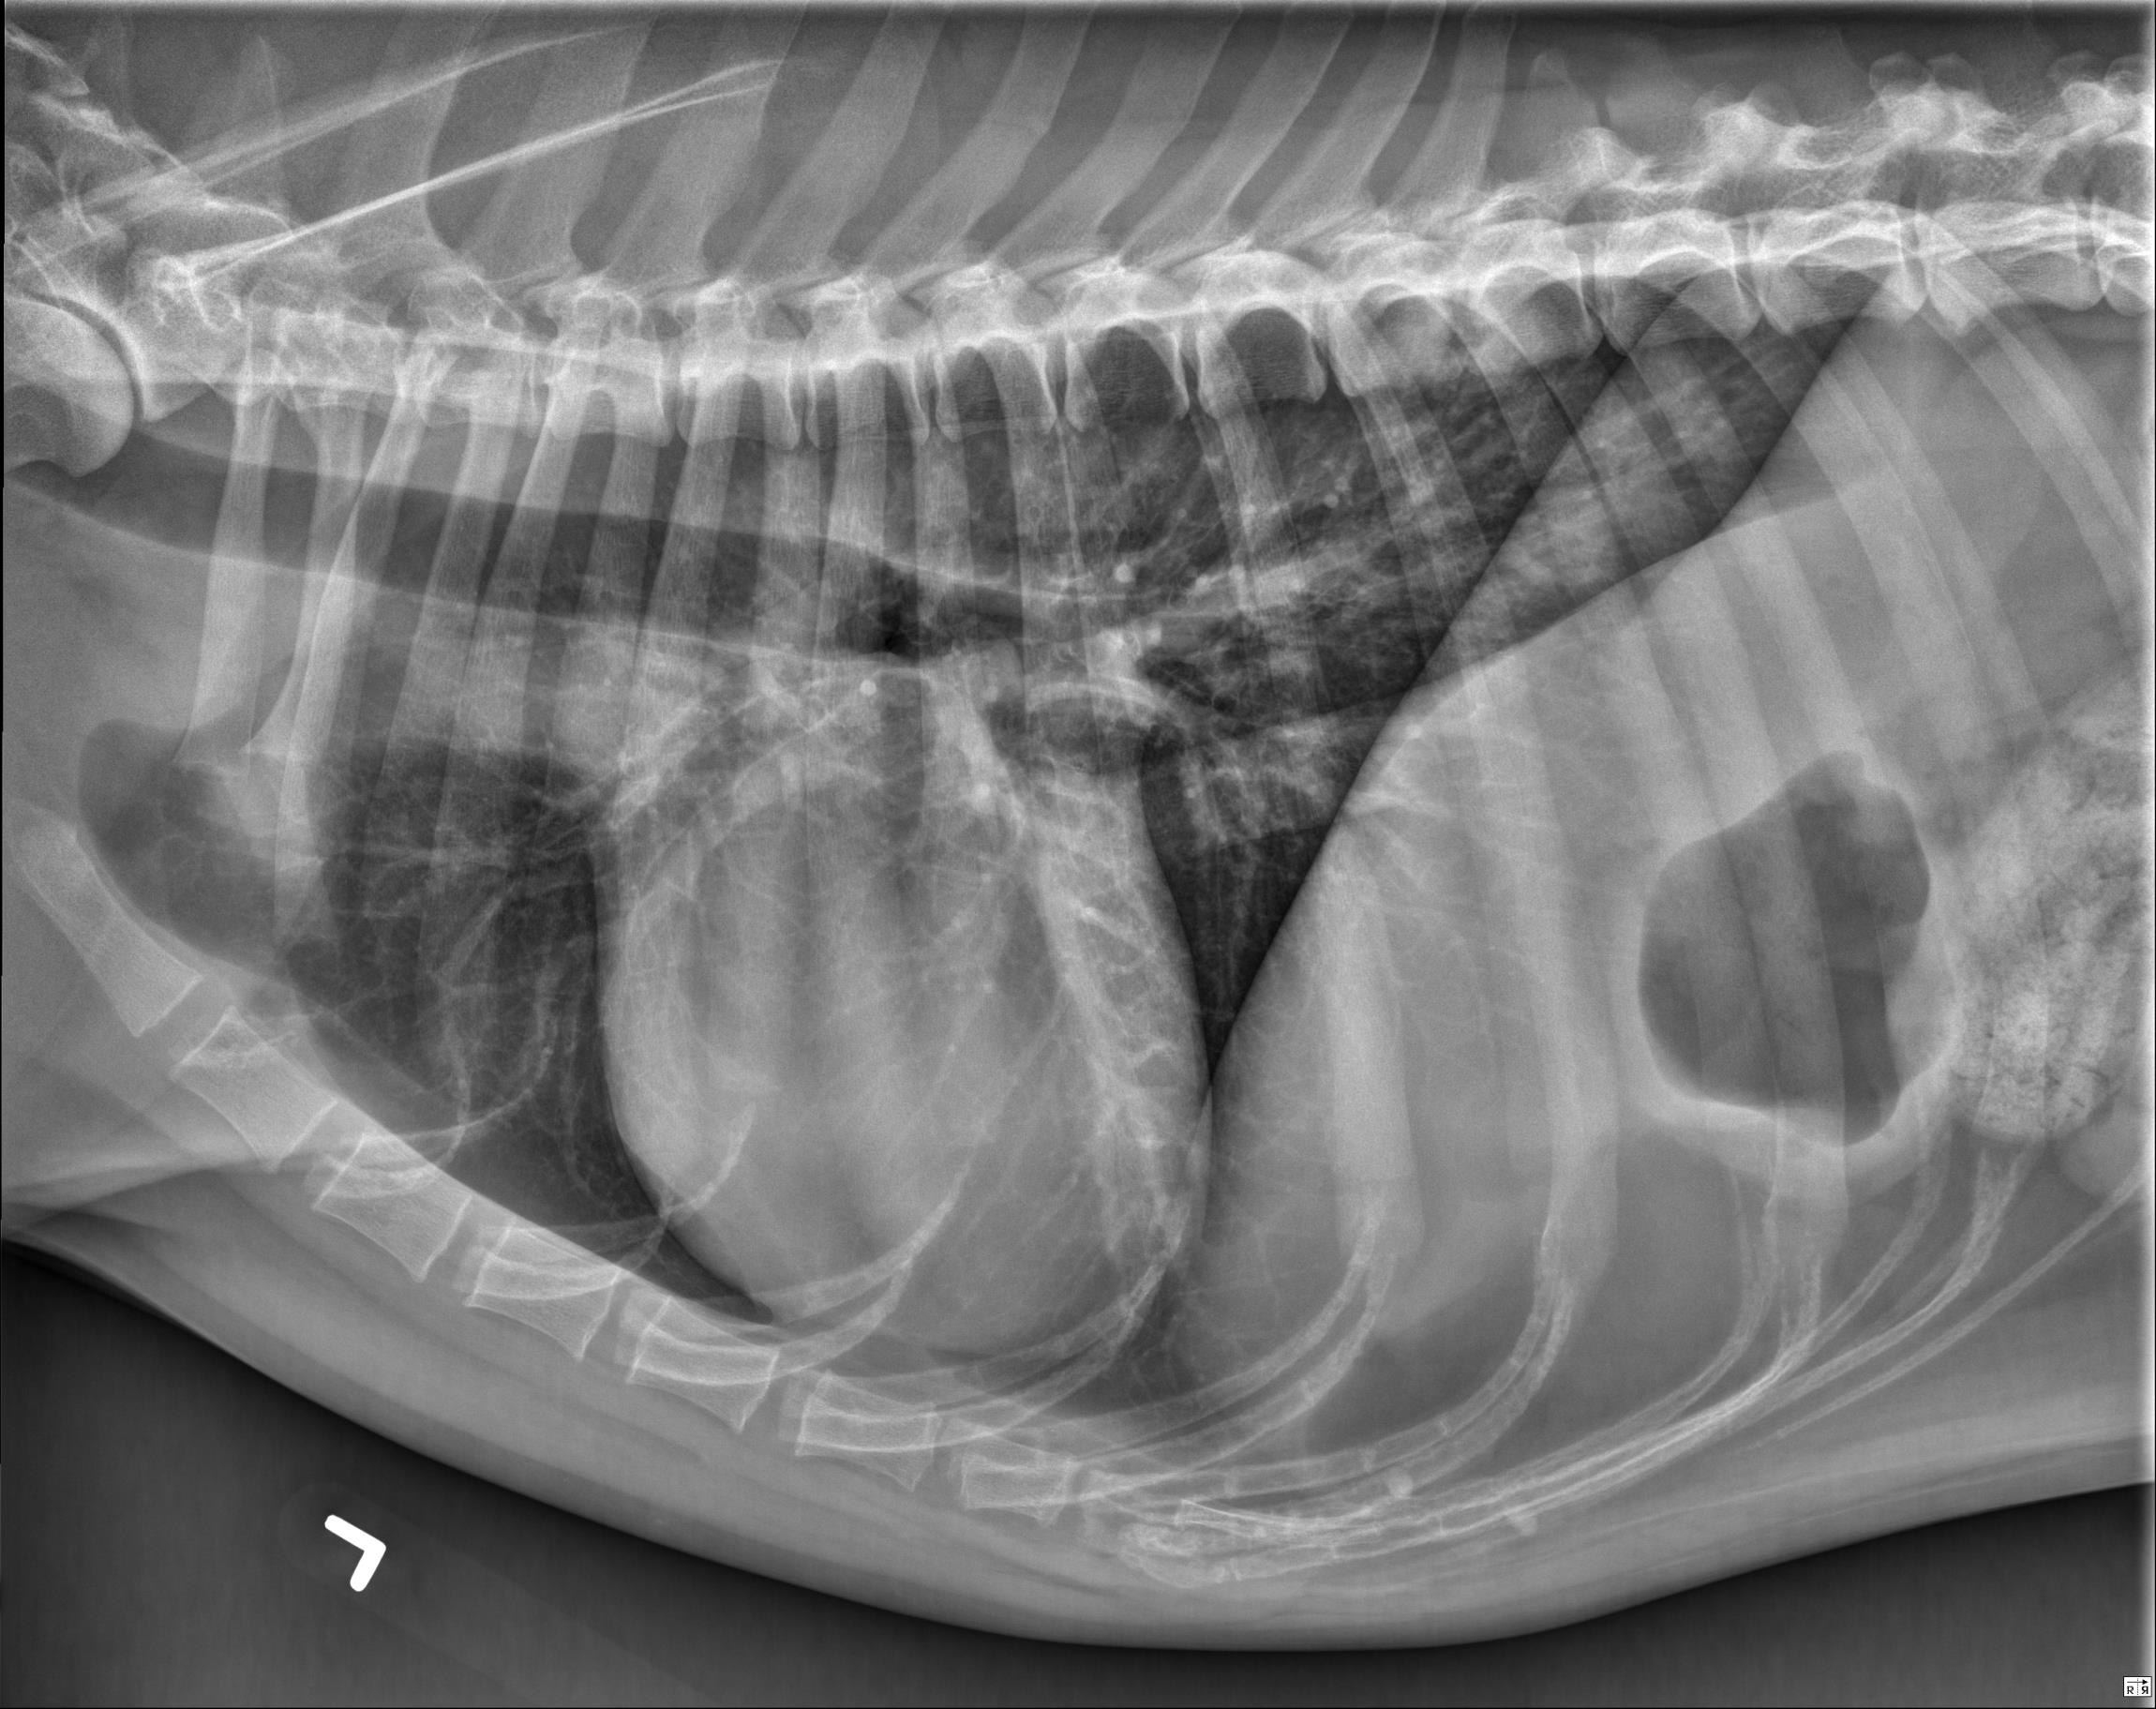

Thorax ventrodorsal and lateral radiographs are available for interpretation.

Thorax: The pulmonary parenchyma is normal. The cardiac silhouette and pulmonary vessels are normal. The pleural and mediastinal spaces are normal.

There is mild to moderate osteolysis of the caudal endplate of T9 and the cranial endplate of T10 which is surrounded by sclerotic bone. The T9-10 intervertebral disc space is narrowed.

The appearance of the T9-10 intervertebral disc space is most concerning for discospondylitis.